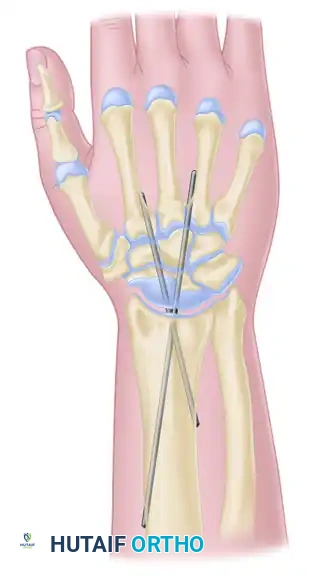

Once the wrist is reduced into the optimal position (neutral flexion, slight ulnar deviation), rigid fixation is achieved using heavy Steinmann pins.

- Transfix the carpus with two stout Steinmann pins measuring 7/64 to 9/64 of an inch in diameter.

- The pins are typically driven in a retrograde fashion. Introduce the pins through the dorsal aspect of the second and third metacarpals, driving them proximally across the prepared carpal mass and seating them deeply into the medullary canal of the distal radius.

- Ensure the pins cross the fusion sites at divergent angles to maximize rotational stability.

FIGURE 72-10 (B): Anteroposterior (AP) schematic illustrating wrist arthrodesis using two crossed Steinmann pins, providing rigid stabilization of the radiocarpal and midcarpal intervals.